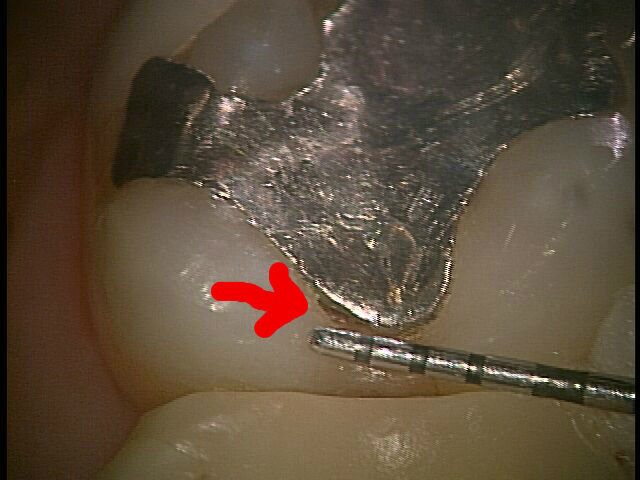

写真は歯を拡大したものですが、歯と歯の間です。片方の歯には金属が入っています。赤い矢印の先に穴が空いていますね。これ、虫歯です。

上の写真の虫歯も、色が黒いだけだったら、私は治療は勧めません。でも、写真の虫歯は穴が空いてそうつまりエナメル質が決壊しているから、治療を勧めるのです。

そして、この虫歯どのくらいの大きさかと言うとわずか1mm

この早期発見に歯科用顕微鏡はものすごい威力を発揮します

ちなみに矢印のところ、銀歯と歯の間に隙間が出来てきています。これも、まあ最初から銀歯が合っていなっかったというのも考えられなくはないですが、長年使う事によって銀歯と残っている自分の歯の磨り減り具合が違うし、金属はたわまないので接着面が剥がれてくるとも言えますよね。